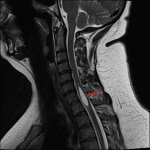

- Syrinx spanning C6-T1 which measures up to 8 mm in diameter

- Syrinx (syringohydromyelia)

Syrinx spanning C6-T1 which measures up to 8 mm in diameter. No abnormal cord signal or spinal canal stenosis.